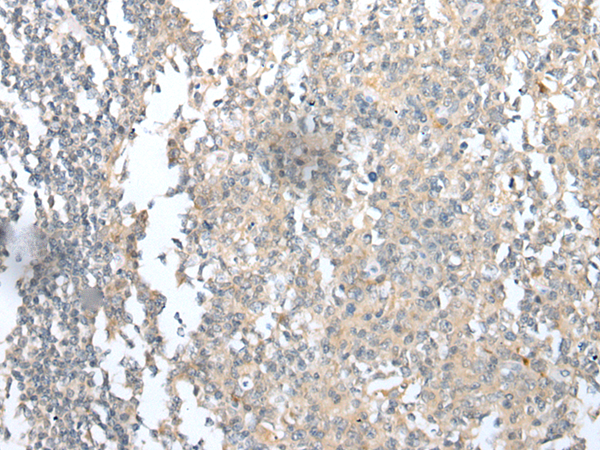

分类: 科研抗体货号: P09110别名: RCDG1应用: IHC反应种属: Human